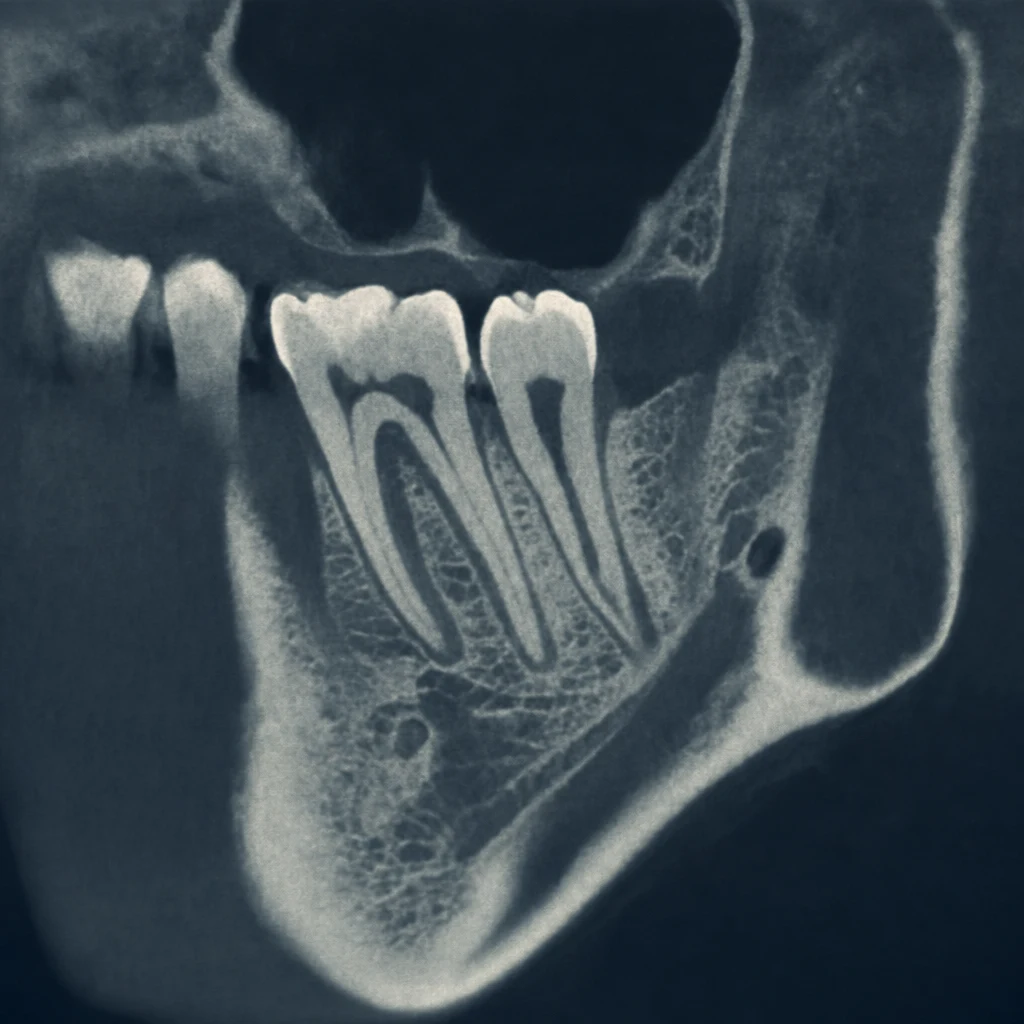

1단계 — 구강 검진 + 파노라마 X-ray

전체 치열·잇몸 상태를 파악합니다. 결손 부위뿐 아니라 다른 치아의 우식·치주 상태, 교합 관계까지 함께 봅니다. 다른 부위 치료가 선행되어야 하는 경우가 의외로 많습니다.

2단계 — 3D CT 촬영

임플란트는 잇몸뼈 안으로 들어가는 시술이라 2D X-ray만으로는 부족합니다. CT로 다음을 확인합니다:

- 잇몸뼈의 폭·높이·밀도

- 신경관(하악신경, 상악동) 위치

- 골이식 필요 여부 판단